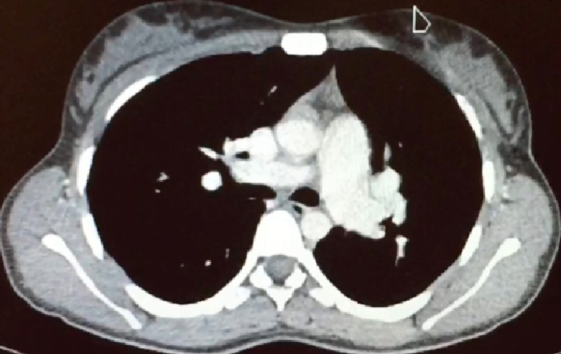

Paciente de sexo femenino, 22 años, sin antecedentes personales a destacar. Consulta en policlínica por cuadro de disnea de esfuerzo (DE) clase funcional II de la New York Heart Association de 6 años de evolución, acompañado de palpitaciones esporádicas. Niega otros elementos patológicos de la esfera cardiovascular. En el examen físico cardiovascular destaca un ritmo regular de 75 ciclos por minuto (cpm), primer ruido normal, desdoblamiento fijo del segundo ruido, soplo sistólico eyectivo a nivel precordial con máxima auscultación en región paraesternal izquierda. Resto del examen físico normal. Electrocardiograma (ECG): ritmo sinusal de 80 cpm que alterna con un ritmo auricular bajo, QRS fino, eje eléctrico medio desviado a derecha (+ 120 grados), bloqueo incompleto de rama derecha (BIRD) (figura 1). En la radiografía de tórax (RxTx) de frente y perfil se observa a nivel de los campos pleuropulmonares una plétora pulmonar y a nivel mediastinal una silueta cardio-aorto-pericárdica aumentada, a expensas de aurícula y ventrículo derecho (VD), con un arco pulmonar prominente (figura 2). El ecocardiograma transesofágico reportó un ventrículo izquierdo de dimensiones normales, con función sistólica conservada, aurícula derecha (AD) levemente dilatada, VD severamente dilatado (diámetro 43 mm) con función sistólica conservada, CIA tipo seno venoso superior de 18 mm de diámetro mayor con pasaje de flujo de izquierda a derecha que asocia retorno anómalo de vena pulmonar superior derecha (VPSD) a la VCS, 10 mm por encima de su desembocadura en la aurícula derecha, con una relación gasto cardíaco-pulmonar/gasto cardíaco-sistémico de 2,8 (Qp/Qs). Hipertensión arterial pulmonar moderada (presión sistólica de la arteria pulmonar 48 mmHg). Dado este último hallazgo, se solicita cateterismo cardíaco derecho que descarta hipertensión arterial pulmonar, informa CIA tipo seno venoso superior, con resistencias arteriales pulmonares (RVP) y sistémicas (RVS) normales con Qp/Qs de 3,13. Se realiza angiotomografía de tórax que evidencia retorno anómalo de VPSD que desemboca en VCS a unos 20 mm por encima de la AD (figura 3).

En esta patología, el shunt está dado tanto por el pasaje de sangre desde el retorno pulmonar anómalo a las cavidades derechas, así como a través de la propia CIA. La magnitud del shunt a través de esta última depende del gradiente de presión entre AI y AD, compliance de ambos ventrículos, relación entre RVP y RVS y la presencia de otras cardiopatías asociadas (valvulopatía mitral-aórtica, cardiopatía isquémica, hipertensión arterial). En general, los pacientes cursan asintomáticos hasta la edad adulta; el 50% presentará síntomas a los 20 años, debido principalmente por disnea de esfuerzo y palpitaciones, siendo menos frecuente la falla cardíaca derecha y la infección pulmonar(1). Con respecto al examen físico, se destaca a nivel cardiovascular un soplo sistólico eyectivo en foco pulmonar debido a hiperflujo y un desdoblamiento fijo del segundo ruido por aumento del tiempo diastólico del VD. Por su parte, los hallazgos electrocardiográficos son concordantes con la presencia del defecto interauricular (ritmo auricular bajo, desviación a derecha del EEM y BIRD). A nivel de la RxTx encontramos claros elementos de remodelado de cavidades derechas, así como signos de hiperflujo pulmonar. El ecocardiograma transtorácico es la herramienta fundamental para definir el diagnóstico y la estrategia terapéutica, permite valorar, entre otros, el tipo, el tamaño, la forma y la relación del defecto con estructuras adyacentes. El hallazgo de un VD severamente dilatado, en ausencia de valvulopatías significativas y patología pulmonar preexistente nos debe alertar de la presencia de un posible shunt interauricular. En este caso, el ecocardiograma transesofágico permitió identificar una CIA tipo seno venoso superior y la presencia de retorno anómalo de vena pulmonar superior derecha desembocando en la VCS. La valoración completa del retorno venoso anómalo debe complementarse con otros estudios de imagen como la angiotomografía de tórax con contraste o la resonancia magnética, donde es fundamental definir, entre otros valores, la distancia entre su desembocadura en la VCS y la AD, para planificar una correcta estrategia terapéutica(1).